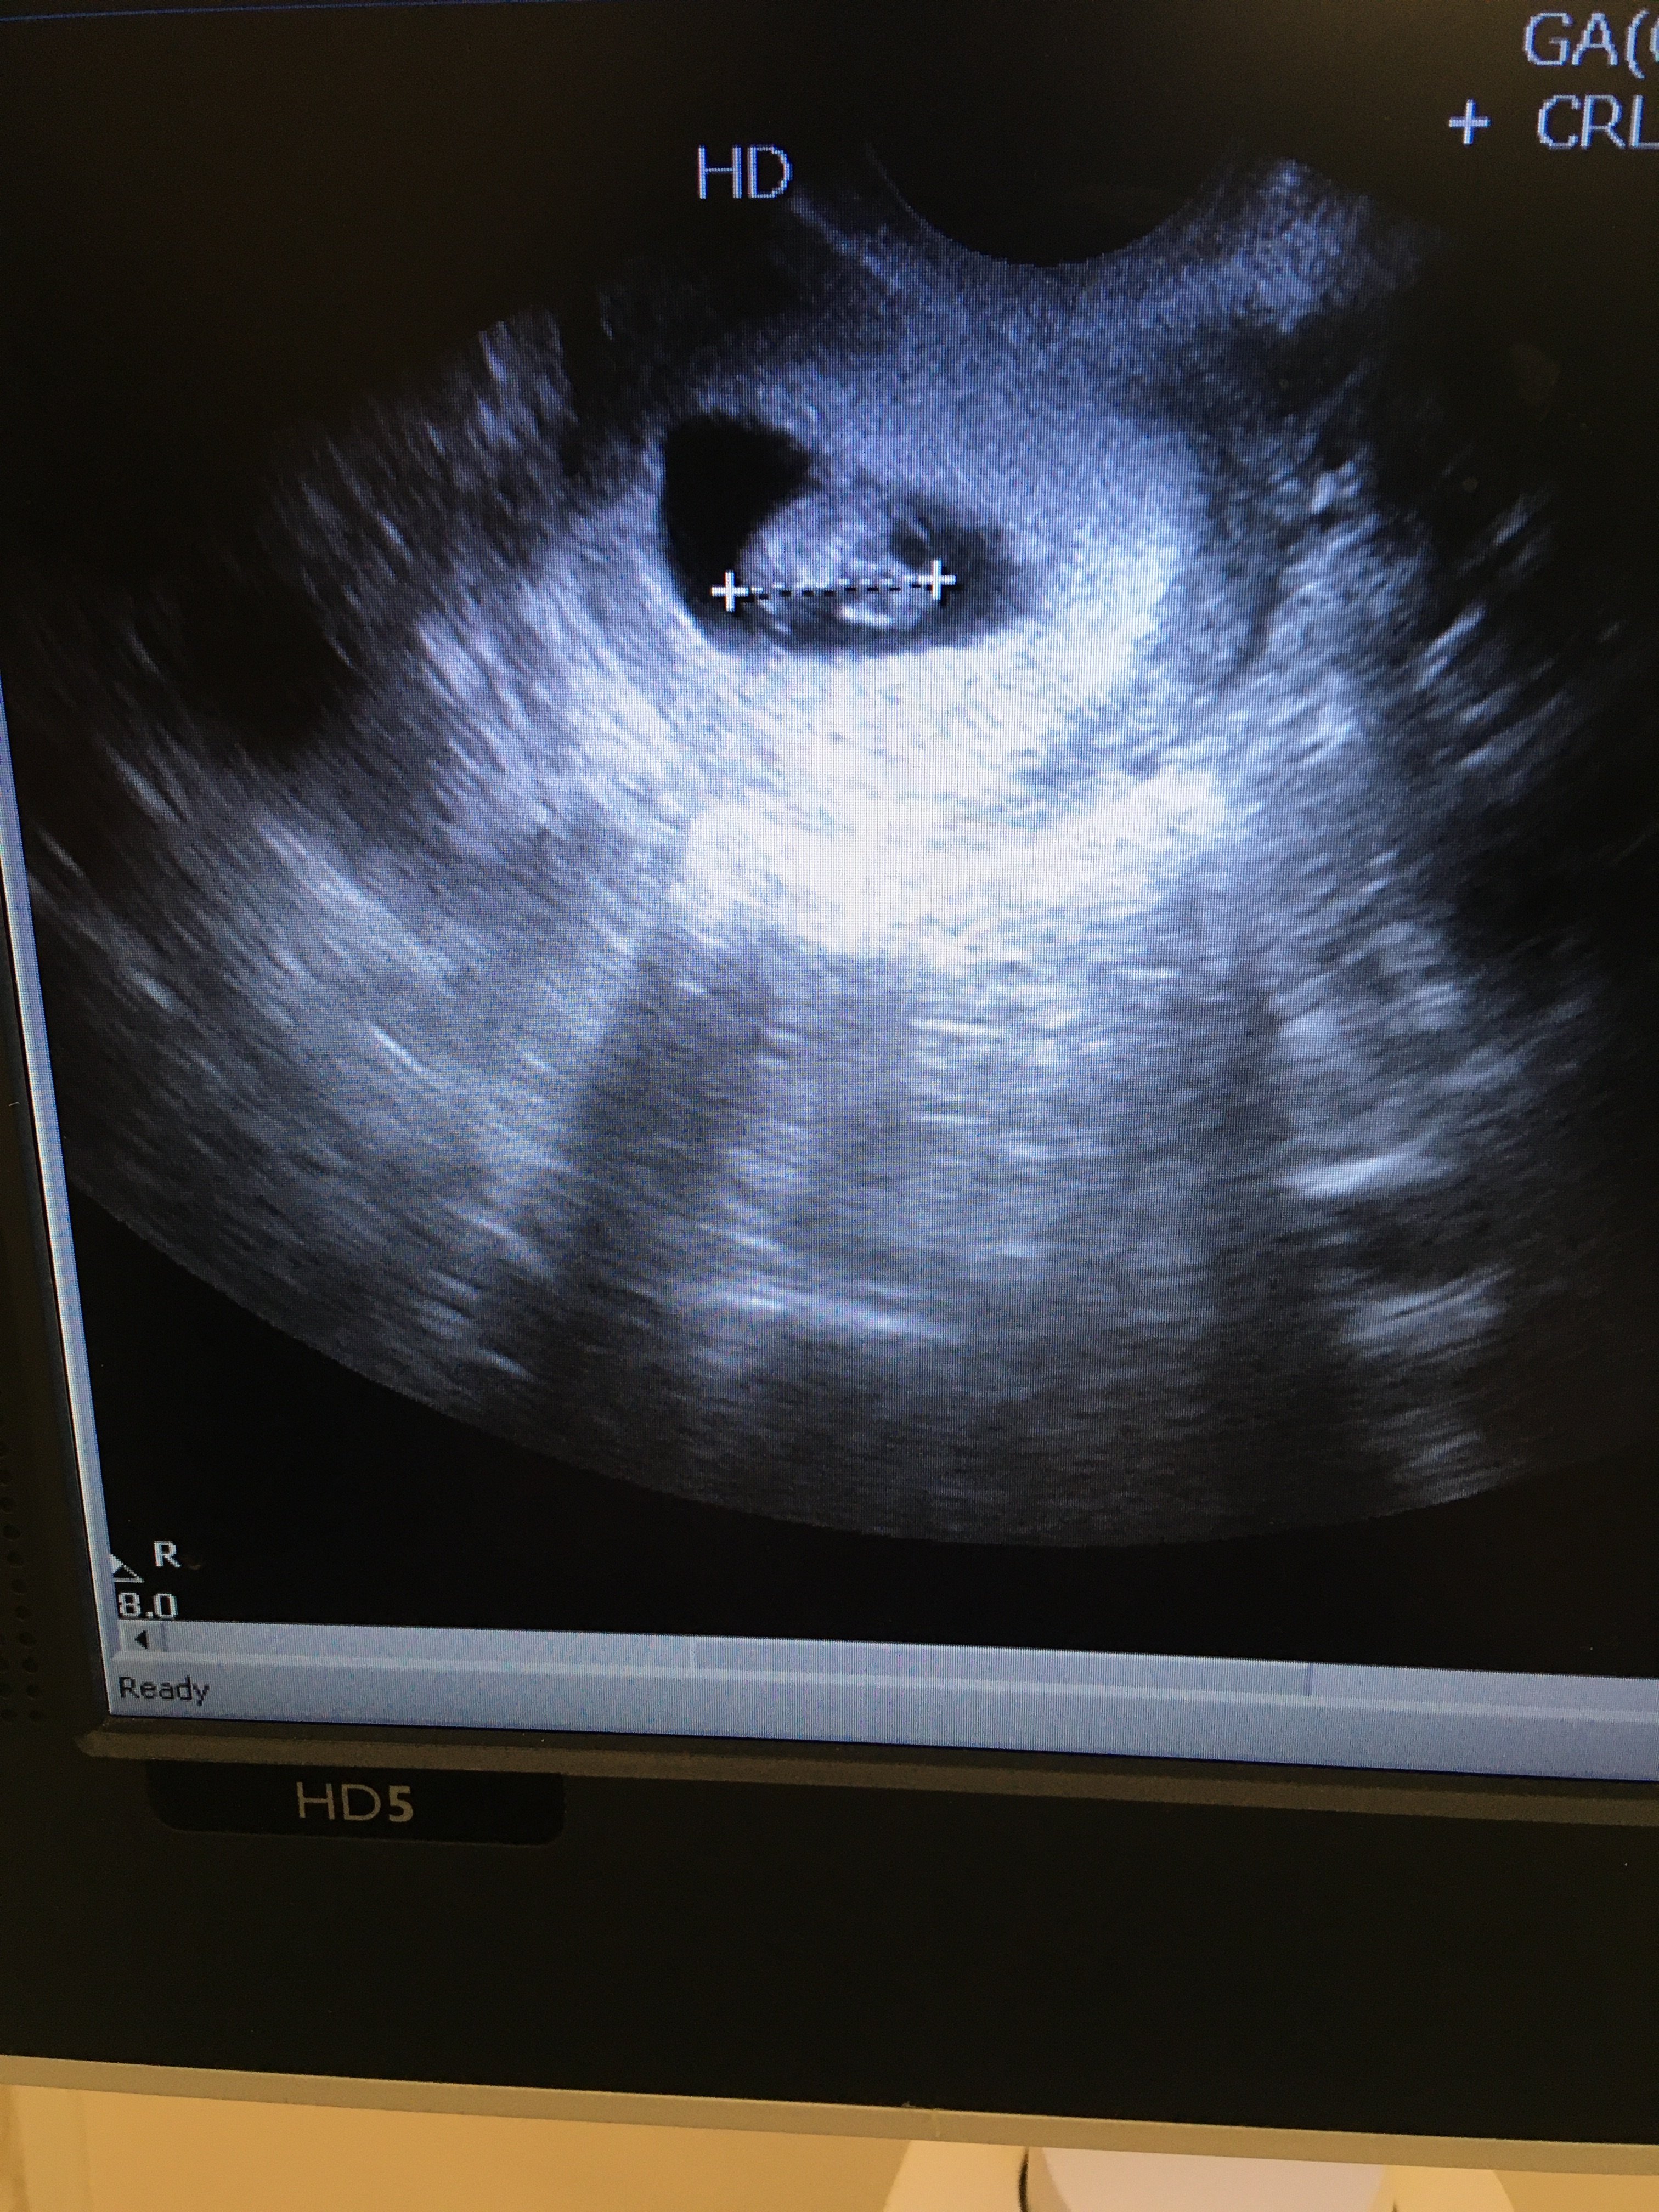

Moje maleństwo 7.2mm z serduszkiem! [emoji173] wg usg 6t4d, czyli 12dni do tyłu w stosunku do ostatniej miesiączki.

Jak siadałam na kozetce, to balam się patrzeć w stronę monitora, a pani doktor tylko chwile poszukała i od razu powiedziała że widać maleństwo, pierwsze co było widać to pulsujące serce. W ogóle lekarz uspokoila mnie z ta wielkością pecherzyka, bo właśnie przy pco i problemach z owulacja bardzo często zarodki pokazują się późno i nie ma co za wcześnie się stresować.

Mam dalej brać duphaston, euthyrox 25, glucophage j prenatal uno, ale dołożyła mi jeszcze luteinę (mam progesteron na granicy) i acard.

Do teraz cala się trzęsę, na chwilkę puściła dźwięk serduszka, to było piękne.Zobacz załącznik 1222917